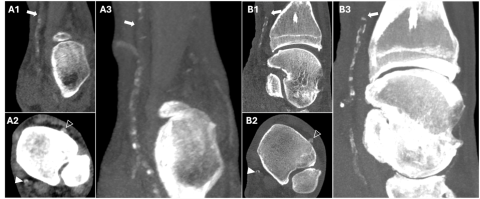

A : Reconstructions multiplanaires conventionnelles DL-DECT, longitudinale (A1) et transversale (A2), avec une épaisseur de coupe de 0,7 mm, et une reconstruction MIP coronale de 10 mm (A3) d'une artère tibiale postérieure calcifiée. A noter l'occlusion proximale du vaisseau (flèche blanche en A1 et A3). Il n'est pas possible de distinguer avec certitude le produit de contraste au sein du segment fortement calcifié. En A2, le vaisseau semble occlus (tête de flèche blanche), mais les artefacts de blooming empêchent la correcte quantification de la sténose. Comparez ce vaisseau à l'artère tibiale antérieure qui est perméable (tête de flèche blanche vide).

B : Images conventionnelles SPCCT avec une épaisseur de coupe de 0,25 mm reproduisant les mêmes vues qu'en A. La réduction évidente du blooming permet une meilleure visualisation de l'absence de contraste au sein du vaisseau, permettant ainsi de poser le diagnostic d'occlusion totale de l'artère plus rapidement et avec un degré de confiance plus élevé.